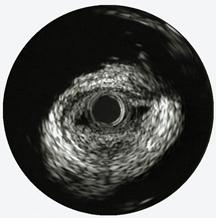

The first three images, courtesy of Professor Takashi Akasaka of Wakayama Medical University and Teruyoshi Kume, M.D., Kawasaki Medical University, shows OCT, IVUS and histological images of the same eccentric fibrous lesion with a calcium deposit.

IVUS’ grainy, black and white images are sometimes hard to interpret, which has given rise to new technical innovations. Ik-Kyung Jang, M.D., Ph.D., Massachusetts General Hospital, assistant professor of medicine at Harvard School of Medicine, said IVUS has a resolution of 65 microns and better resolution is needed to visualize certain structures, including identifying components that make up vulnerable plaque.

“If you want to detect fine structural changes, such as vulnerable plaque, IVUS does not have enough resolution,” Dr. Jang said.

“The biggest advantage with OCT is the resolution, which is 10-15 microns,” Dr. Jang said. “If you put IVUS and OCT images next to each other the difference is night and day.”